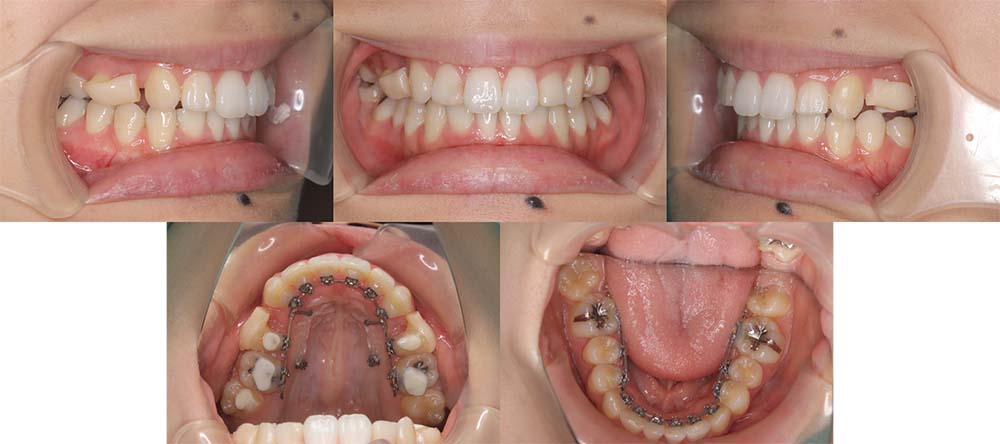

| 症例分類 | 叢生 |

| 診断名 | 上下叢生 |

| 主訴 | 八重歯と下の歯のガタガタが気になる |

| 年齢 | 24歳4ヶ月 |

| 性別 | 女性 |

| 抜歯部位 | 上下左右の第一小臼歯(4本) |

| 使用装置 | 上は裏側、下は表側のワイヤー装置 |

| 治療期間 | 2年8ヶ月 |

| 保定装置 | 固定式保定装置、取り外し式保定装置(8時間) |

| 費用 |

[検査・診断料] ¥49,500 [基本施術料] ¥1,056,000 [調整料] ¥5,500/回 [抜歯] ¥5,500/本 [保定装置] ¥55,000(税込) 抜歯や虫歯治療は他院にて費用が別途かかります。(抜歯¥4,000〜10,000/本)

上下叢生のため、上下第一小臼歯を抜去して上裏側下表側のハーフリンガルで治療しました。

顎間ゴムは治療期間の半年程度使用しましたが、協力度が良好だったためしっかり咬合することができました。

治療開始前にホワイトニングをしたこと、咬合力が強いためか装置の脱離が多く、予定より治療期間が伸びてはしまいました。